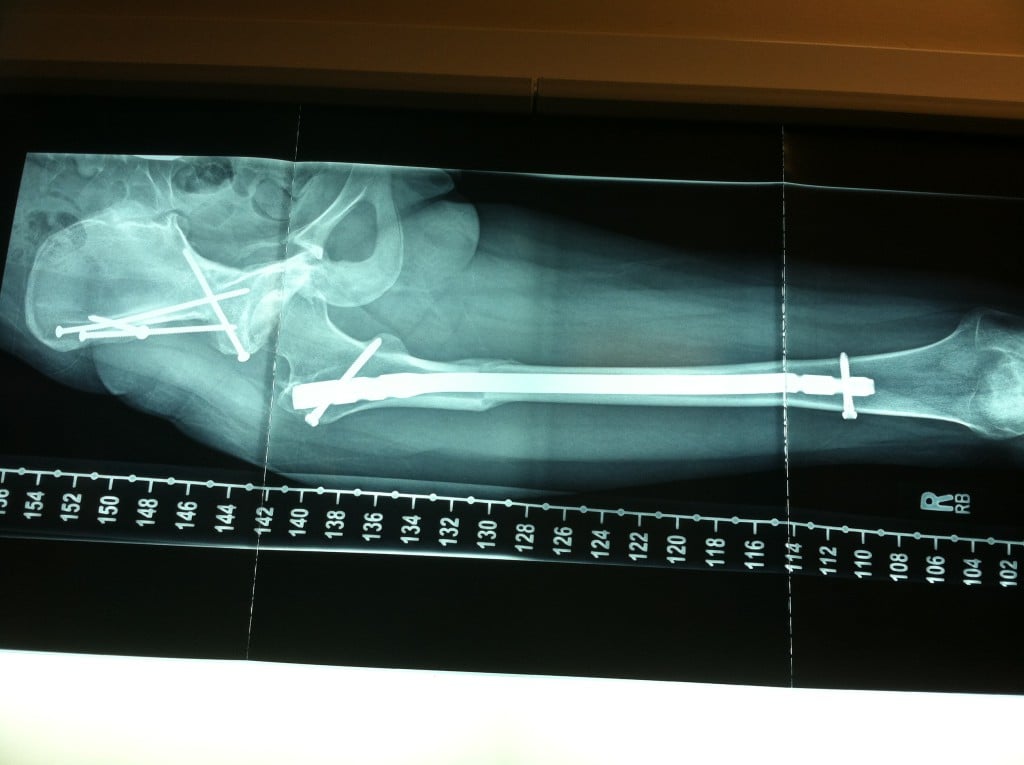

After a few years of hip pain and feeling like my hip popped out of joint, I consulted Dr. Thane Morgan, an orthopedic surgeon in Amarillo, TX who diagnosed a labral injury as well as hip dysplasia and impingement. He referred us to a hip specialist in Oklahoma City (Dr. Hal Martin, now at Baylor in Dallas, TX), who did the arthroscopic labral repair in March, 2012, when I was 16. He told us that I would likely need an osteotomy to correct the dysplasia if it "popped out" again. Dr. Martin referred us to Dr. Robert Buly at HSS after my right hip popped out in November, 2012. We met Dr. Buly for the first time January 7, 2013 and immediately had a strong sense of trust and rapport with him and his nurse Elaine. He laid out a plan to end my hip pain with the help of Dr. David Helfet, who took time out of his busy schedule to meet with us that same day. They would do both a periacetabular osteotomy PAO (cut the socket loose from the pelvis, rotate it to cover the joint, re-attach with 4 big screws) and a femoral de-rotation osteotomy (cut the femur in two, rotate the ball to the correct angle, insert a titanium rod and attach screws top and bottom) to correct malformation of my right hip. He also explained that if my left hip ever began causing pain, I would probably need a femoral osteotomy to correct it as well. My left socket had better coverage, so would likely be fine. As of this writing Dr. Buly has done three surgeries for me: the original right hip PAO and femoral de-rotation osteotomies on 2-28-13 (along with Dr. Helfet); removal of hardware on the right hip on 12-18-13; and most recently, left hip femoral de-rotation osteotomy on 12-16-14. I now am able to walk pain-free at the age of 19 and am extremely grateful! I have gone through months of rehabilitation with these surgeries, and am an expert on crutches...but it has all been worth it! I will have one more removal of hardware surgery and hope to be "finished"!